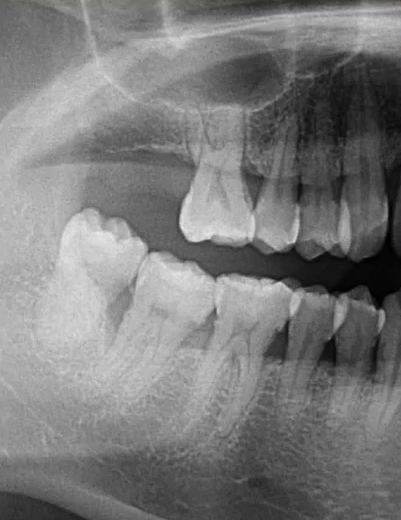

因为曲面断层片反映的是上下颌牙齿、上颌窦、关节,在一张片子中所展示的解剖结构较多。比如刚才的片子,最容易诊断的是右下6远中邻面深龋合并根尖周炎,左下有埋伏的多生智齿,右侧是垂直智齿。

4、智齿阻生

治疗:拔除

检查:颌骨评估、阻生齿评估、邻牙评估